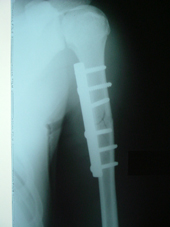

| Fracture Femur |

Interlocking nailing femur |